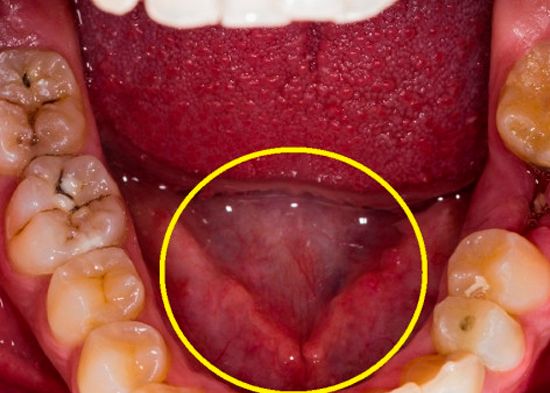

4 tipos de virus que pueden permanecer “dormidos” y reactivarse en cualquier momento

Cuando comenzamos a presentar síntomas de una enfermedad viral, lo primero que pensamos es en el momento que pudimos contraer la infección sin imaginar que quizá siempre estuvo ahí, escondido en alguna parte de nuestro cuerpo esperando pacientemente para reactivarse. ¡Tal como lo lees! Descubre 4 tipos de virus que pueden permanecer “dormidos” por décadas.